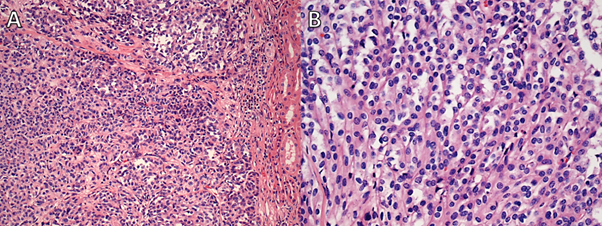

Figure 6

Figure 6. Case 2: A. Low-power and (B) high-power fields showing mucinous tubular and spindle cell carcinoma.